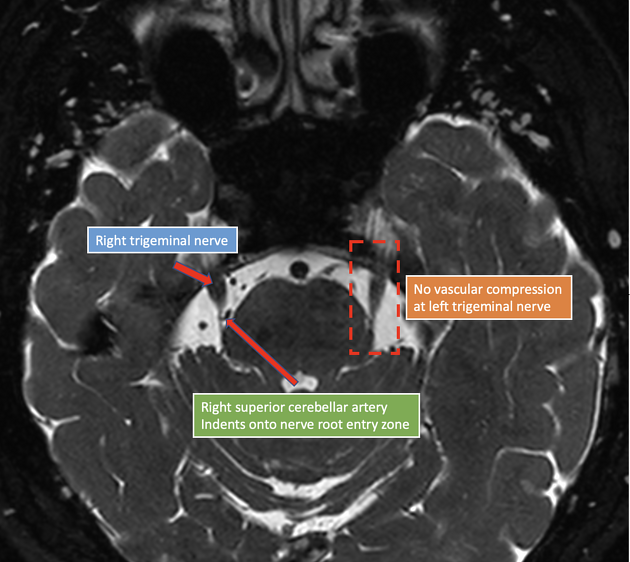

You get neurovascular compression of the root of the trigeminal nerve.

This happens at the root entry zone, usually by the superior cerebellar artery.

You need to see this compression on MRI to confirm the diagnosis.